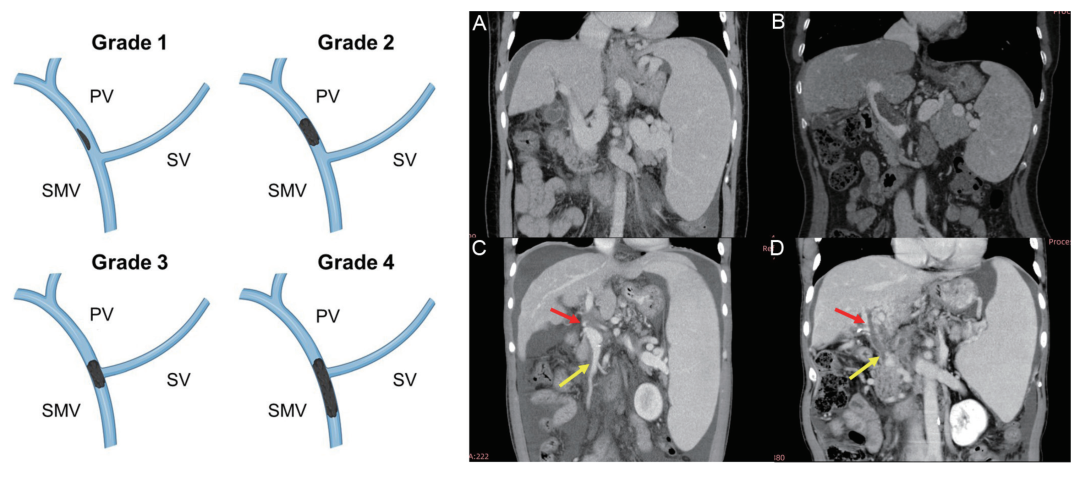

在基线时,共有 45 例(26.6%)患者合并 PVT。根据Yerdel 分级(图2),其中Ⅰ级 10 例(22.2%)、Ⅱ级 17 例(37.8%)、Ⅲ级 2 例(4.4%)、Ⅳ级 6 例(13.3%)。另有 10 例患者的血栓仅局限于门静脉、脾静脉或肠系膜上静脉分支,故未纳入 Yerdel 分级。

图2 门静脉血栓的Yerdel分级示意图及影像学表现